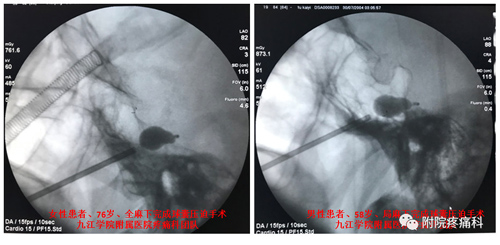

三叉神经球囊压迫术手术方法简单,在X线透视监视下,将一个微球囊导入Meckle’s腔的三叉神经的半月节,然后缓慢注入对比造影剂充盈球囊,把导致三叉神经痛的神经纤维解除卡压、并通过扩张的微球囊压迫破坏,最后退出球囊,拔出穿刺针。术中病人耐受性良好,在全麻下接受整个手术,没有疼痛和不适感,伤口小(针眼大小), 手术时间短,术后疼痛立即缓解率可高达95%以上, 当天即可下床活动,基本不影响术后进食,并发症发生低。该手术适应症广,除了原有射频热凝术的适应症,对原发性三叉神经第一支疼痛、射频热凝术后效果欠佳的病人都有效,具有综合其它手术的优点:微创、安全、有效、风险小、不易复发。该手术因人性化、舒适度高、恢复快、病人接受度高,在欧美发达国家已广泛开展。